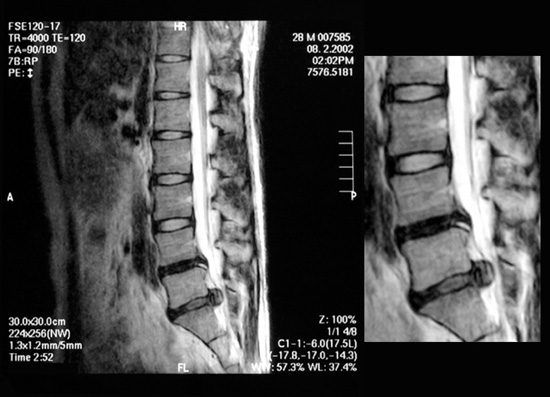

ヘルニアMRI画像

掲載した椎間板ヘルニアMRI画像は現在『指圧研究会・咲晩』メンバーであるT.H君の中学時代からの友人(ケン氏)より提供されたものです。典型的な腰椎椎間板ヘルニアで明白な坐骨神経痛の症状を呈していました。外科手術で対応されることの多いケースだと考えます。

はじめまして。28才で会社勤めしています。二年前(2000年3月)にテニスをしている最中に突然腰に激痛が走り、3日間寝たきりになりました。今まで大きな怪我や病気を家族もしたことが無く、自分の判断で自然治癒にまかせて生活し、テニスも続けてきました。二年前にしていた仕事は製造業で、一日中腰を曲げて作業することが多く、重いものもたくさん運びました。2001年の7月くらいから接骨院に通い始めました。いろいろな所で診てもらいましたが、腰痛はよくなりませんでした。今年の6月位から左腰と左足の痛みが悪化し、歩くことが困難になりました。夜も痛みで眠れなくなり大変な思いをしました。整形外科でMRIを進められた結果、椎間板ヘルニアと診断されました。この時のレントゲンのコピーを今でも持っていますが、4、5番目の椎間板が飛び出し神経を圧迫している様子がはっきりと写っていました。整形外科の先生の説明によると、10人に1人か2人はほおって置いてもヘルニアがひっこんでしまうことがあるそうです。自分みたいに大きなヘルニアが治ったのは今までみたことがないから、少し様子をみて手術をおすすめしますと言われました。中学の頃からの友人が、現在指圧の専門学校に通っているので相談したところ、静岡県内にある浪越流の指圧の先生を紹介してくれました。1、2週に一度のペースで土曜日に山梨県の甲府市から4時間半かけて通っています。今日で合計6回みてもらいました。先生にはこのペースでヘルニアを何とかするのは虫がよすぎるって言われていますけど、効果があって足の痺れは無くなり、かなり回復してきています。先生からの説明の中に、10人腰の痛い人がいれば、10人様々原因があって(姿勢・職業・体質など)10人治し方も違ってくので、患者一人一人の体を知るために出来るだけ多く足を運んでもらって原因を把握して、その人に合う治療を施していくとのことです。腰が痛いから腰だけを治療するのは、治療と言うよりむしろ慰安だともおっしゃっていました。腰痛に限らず、体の一部が痛いと言うことは患部とそれ以外の原因があるので、それをきちんと治していかなければならないそうです。今私がしてもらってることは背中とお腹と膝の上とお尻の横側などを中心に指圧してもらってます。骨盤の矯正も少しし始めています。(表現が分かりづらくてすみません)ヘルニアで悩んでるみなさん!ヘルニアになってしまってもスポーツが満足に出来るようなところまで回復している人がいることも事実です。私は浪越流の指圧師に診ていただいてよくなってきていますが、みなさんも希望を持って自分にあった治療をしてくれる所に巡り会えることを願っています。長々と語ってしまい申し訳ありませんでした。

- MRI検査:ヘルニアの診断